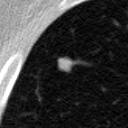

The current study focuses on lung nodule retrieval from a database of CT scans, where patches taken from CT slices of pulmonary nodules are to be mapped into an embedding. LIDC-IDRI [5] is a dataset of thoracic CT scans of 1,010 patients. All the scans were annotated by up to four radiologists, where each one identified, segmented and evaluated separately the lung nodules of a diameter above . Their evaluation also included ratings for a set of 9 characteristics: Subtlety, Internal structure, Calcification, Sphericity, Margin, Lobulation, Spiculation, Texture and Malignancy. The rating system was based on a discrete score of 1-5. Four examples of nodule patches are illustrated in Figure 2: 2 benign (a, b) and 2 malignant (c, d). A rounded vector of the mean rating is bellow each nodule, with the characteristics ordered according to the listing above. The most prominent difference between a and b is the calcification: 3 (solid) and 6 (absent) accordingly. d compared to c has a more defined margin, is more lobulated, but less spiculated. The malignancy score is used to define malignancy classes: score of 1-2 is benign, score of 3 is unknown, and a score of 4-5 is malignant.

(a) Benign

3, 1, 3, 3, 4, 3, 1, 5, 1

(b) Benign

3, 1, 6, 5, 5, 1, 1, 5, 2

(c) Malignant

5, 1, 6, 3, 3, 4, 1, 5, 5

(d) Malignant

4, 1, 6, 3, 4, 2, 2, 5, 4